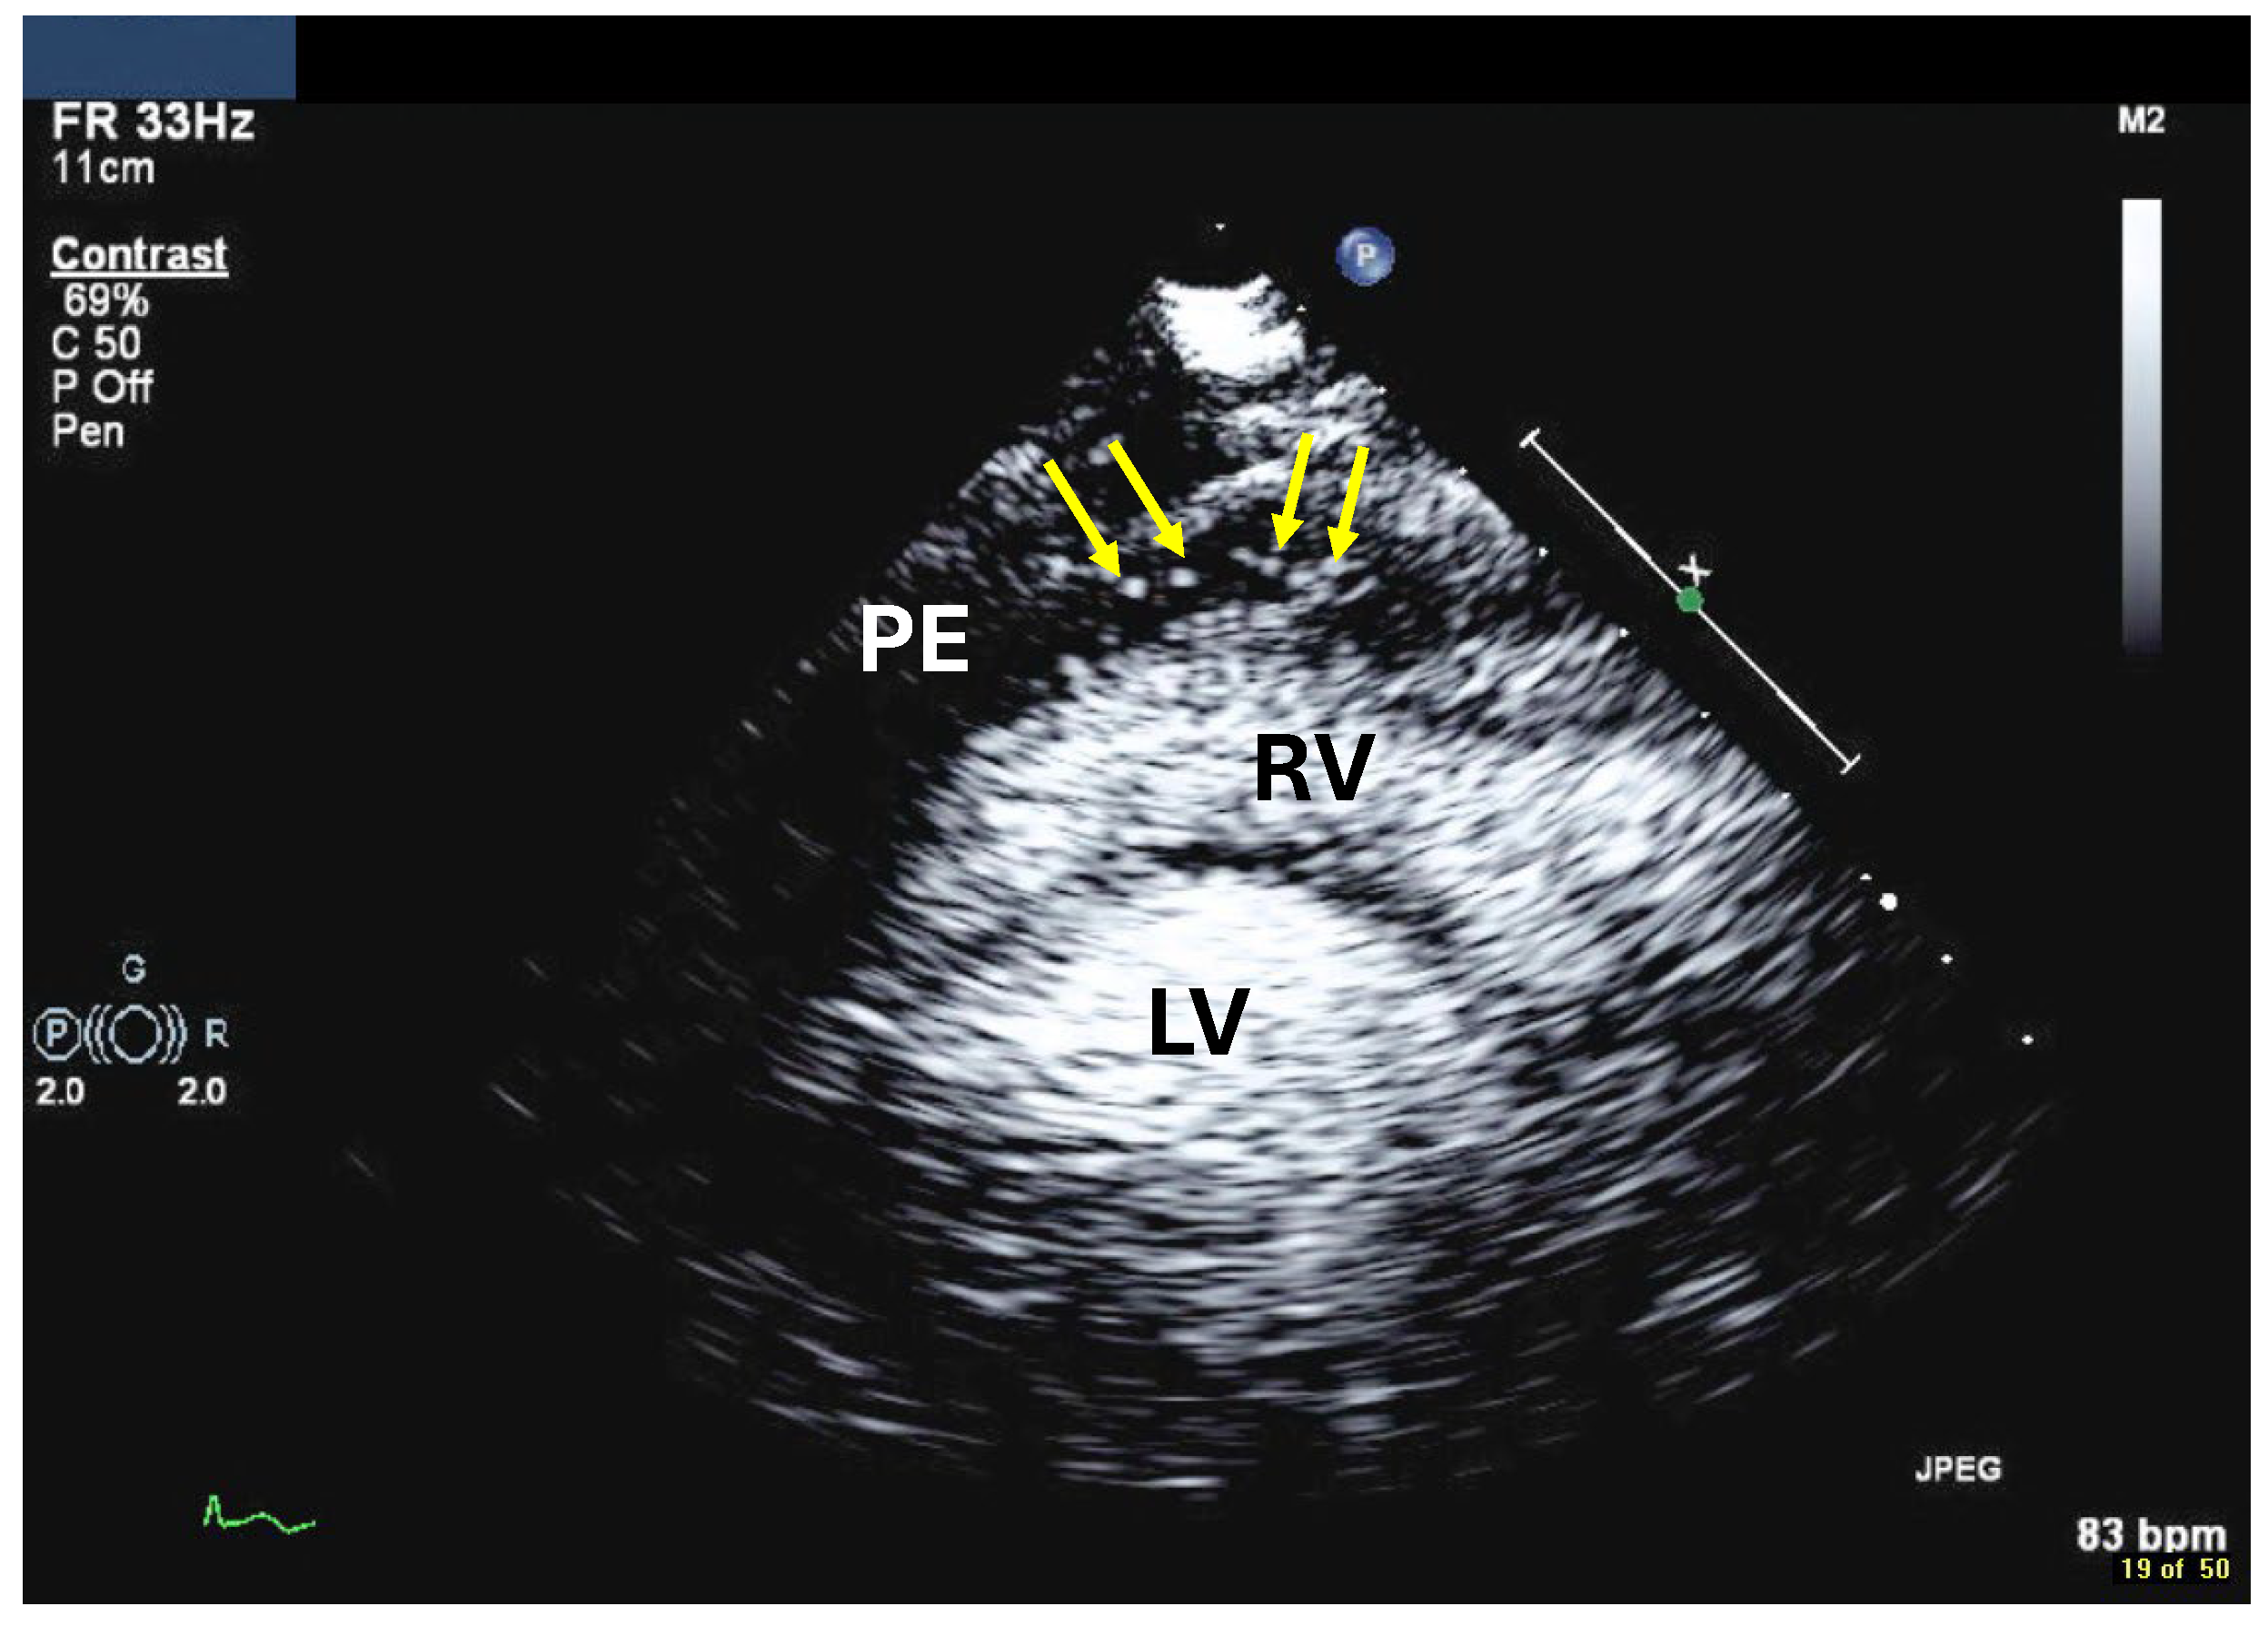

| Imaging method | Low-MI-contrast-specific imaging, alternatively intermediate-MI-contrast-specific imaging |

| Imaging planes | First try subcostal view, then standard views |

| Contrast application | Bolus injection |

| Typical findings | Usually isolated bubbles in the pericardial fluid Review frame by frame! |

| Alternative imaging | Cardiac computed tomography with contrast |